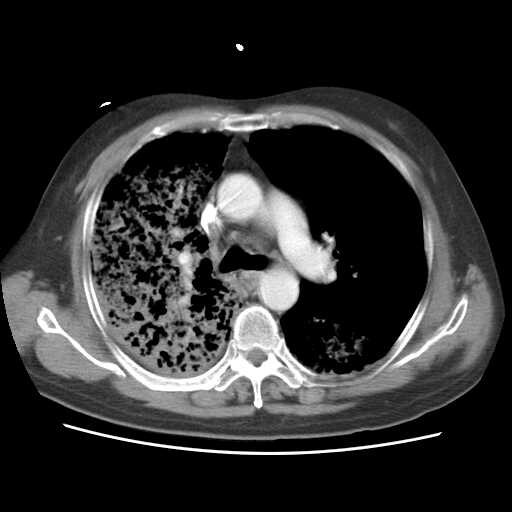

2008.8.17ct

病变从8.11-8.17明显改变,增多,以蜂窝状改变为主,类蜂窝肺,似弥漫性肺泡癌,但是病变进展太快,不符合弥漫性细支气管肺泡癌。因此考虑为特殊微生物感染,多以霉菌类常见,建议细菌微生物学检查。

疑点二:影象表现怪异,大片阴影内见多发筛孔征,如何解释.

间质为主,血管炎性水肿?

结合临床慢支炎肺气肿,肺心病病史,三次胸片观察可见病情发展变化迅速,病情凶险,考虑多重感染伴ards.